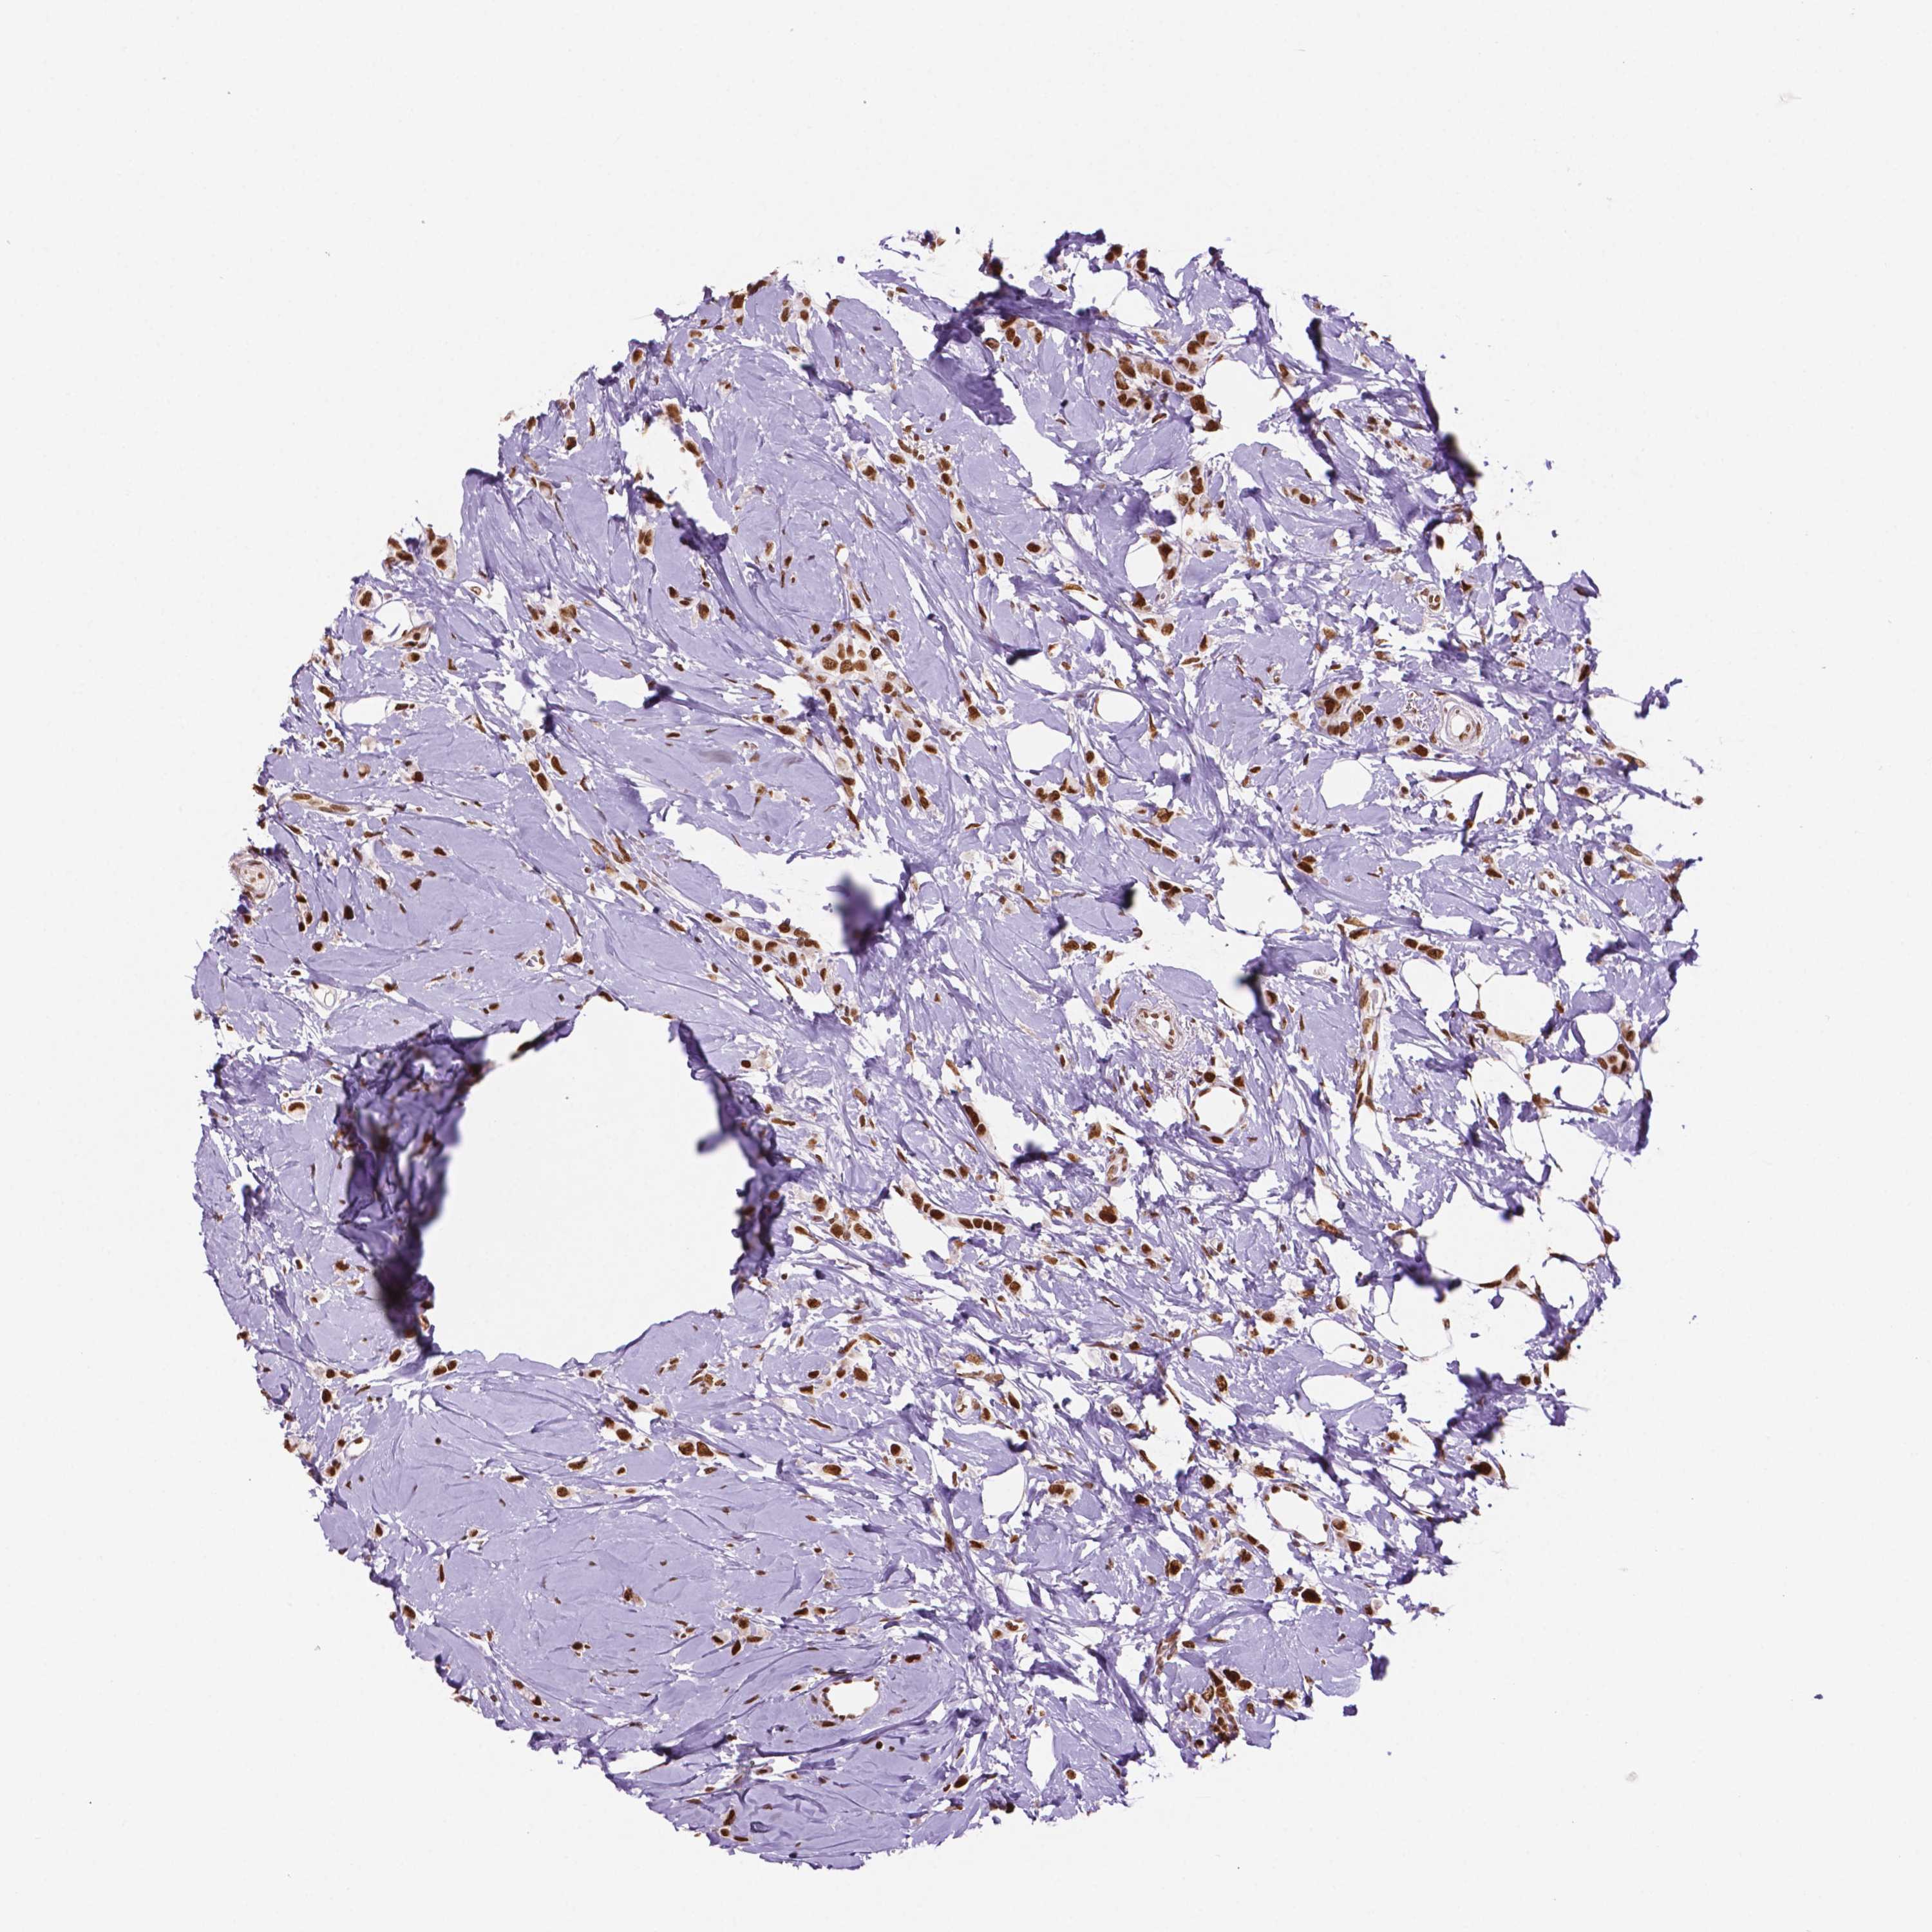

CANCER BREAST CANCER Show tissue menu

BRCA TCGA BRCA VALIDATION PROTEIN EXPRESSION